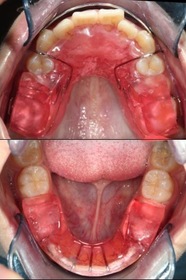

蔡醫師讓張小弟戴上『活動式功能矯正器』,

這是可拆式的,

主要是促進下顎的生長,補足下顎的發育不完全。

上圖:下顎短小,有深咬的情況,病患會誤以為暴牙。

下圖:經過五個月的時間,張小弟的咬合情況已改善不少。